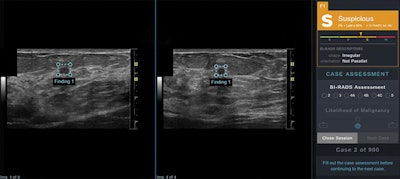

AI output scores were presented to study readers in graphical form as an electronic case report in conjunction with orthogonal ultrasound images of the lesion for that case. Right panel shows categoric assessment, in this case "suspicious," with triangle marker indicating confidence of assessment within that category. In this example, the AI software correctly classifies this lesion as suspicious; malignancy (invasive ductal carcinoma) was confirmed by ultrasound-guided biopsy. LoM = likelihood of malignancy, B = benign, P = probably benign, S = suspicious, M = probably malignant. Images and caption courtesy of the American Journal of Roentgenology.Four weeks later, the readers again reviewed the 900 studies, but in the opposite format from the first session.